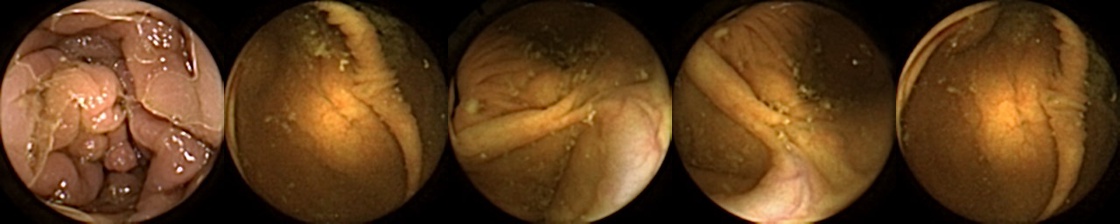

Refer to caption

Figure 1: Positive exemplar images with each row showing five images of a unique polyp, where in each row, the first image corresponds to first partial and fifth image is the last full view of the same polyp. The polyps have been marked in green for each image.

For MIV, we construct both positive and negative exemplar pairs from this multi-patient polyp image dataset. Positive exemplars are constructed based on the five images from a single polyp, with one of the second, third, or fourth image designated as the query and the remaining four images forming the target bag. Images from five example polyps are shown in Figure 1. Negative exemplars are constructed using a more sophisticated strategy: if a patient has multiple polyps, the query image is selected from one of those polyps at random, while target images are sampled from other polyps of the same patient; if a patient has only one polyp, target images are drawn from different patients entirely.